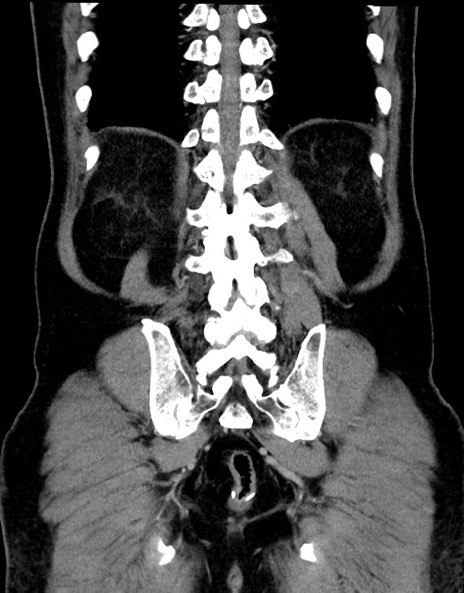

横断像

【症例】70歳代男性

【主訴】腹痛

【現病歴】今朝から腹痛あり。全体的に痛い。特に左上の方。排ガスが今日はない。冷や汗が出る。

【既往歴】直腸癌術後

【身体所見】左側腹部〜上腹部に圧痛あり。腹膜刺激症状明らかなではない。軽度反跳痛。左下腹部に術後瘢痕あり。

【データ】WBC 7700、CRP 0.02